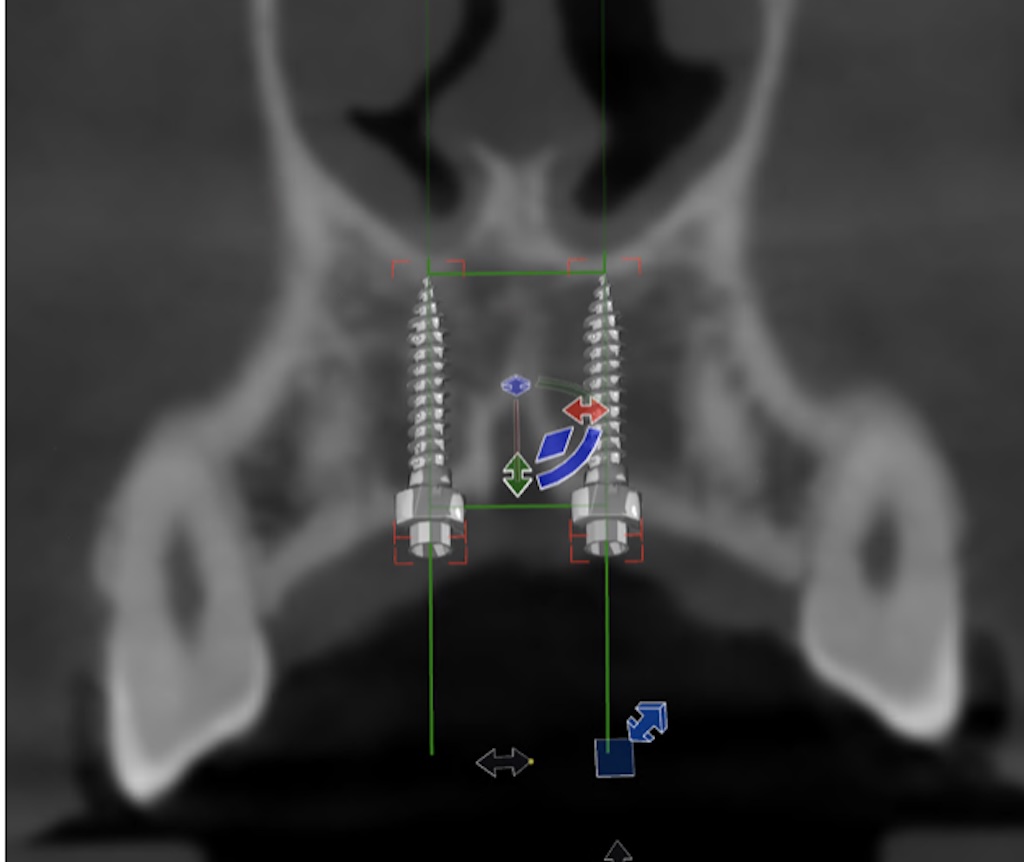

• Prezentacja pozycjonowania mikroimplantów w programie OnyxCeph

szkolenie in-office pozycjonowanie mikroimplantow